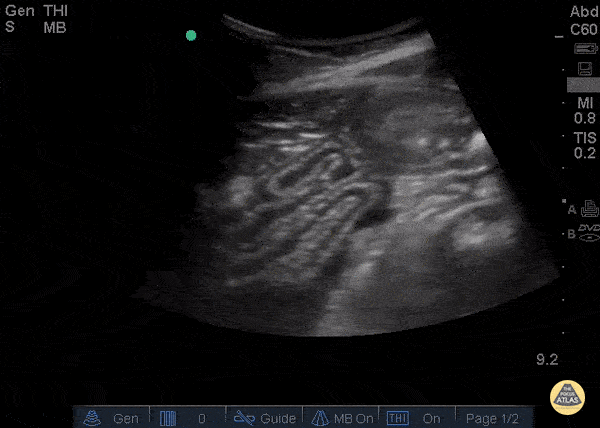

Bowel-GI - Free fluid and Collapsed Bowel

23 year old male with no known medical history s/p surgery for sigmoid volvulus presenting with severe lower mid-abdominal pain. Ultrasound showed trace free fluid and significant collapsed bowel with no peristalsis. CT scan findings were equivocal to our US findings. Patient was found to have bowel dehiscence in the operating room. Bowel wall is most easily seen when there is free fluid or ascites. Normal bowel has layered appearance, easily compressible with intermittent peristalsis. The most frequent pathological findings found by ultrasound is wall thickening, mucosal abnormalities, the absence of peristalsis (1). One benefit of point-of-care intestinal ultrasound is decision for early surgery. Sonographic findings suggesting a need for surgery include; intraperitoneal free fluid, bowel wall thickness of more than 4 mm, and decreased or absent peristalsis (2). Valette PJ, Rioux M, Pilleul F, Saurin JC, Fouque P, Henry L, Eur Radiol. 2001; 11(10):1859-66. Grassi R, Romano S, D'Amario F, Giorgio Rossi A, Romano L, Pinto F, Di Mizio R, The relevance of free fluid between intestinal loops detected by sonography in the clinical assessment of small bowel obstruction in adults. Eur J Radiol. 2004 Apr; 50(1):5-14. Dr Catharine Bon and Dr Bobak Zonnoor Kings County Emergency medicine